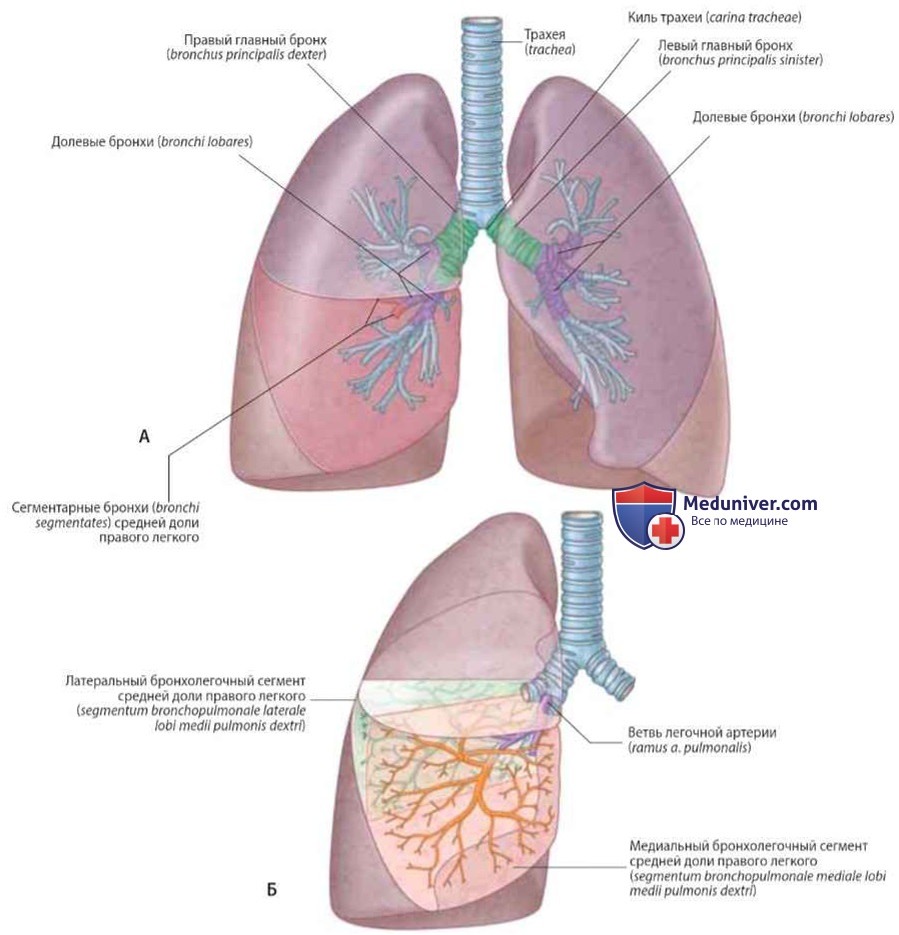

Анатомические изображения сегментов легких различных животных

Раздел: Другие животные